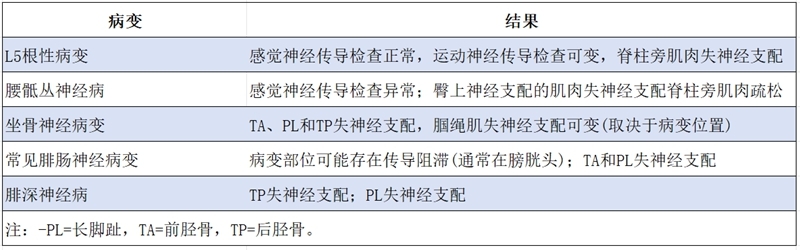

足下垂的特征性电诊断结果

相关解剖

主要病因

中枢神经病变:脑梗死、脑肿瘤和脊髓异常等。

周围神经病变:L5神经根、坐骨神经、腓总神经、腓深神经、腓浅神经。

L5神经根瘫的诊断

主要可通过病史、症状、体征、影像学检查:MRI和特殊检查:EDX Testing确诊,另外还需注意鉴别诊断。